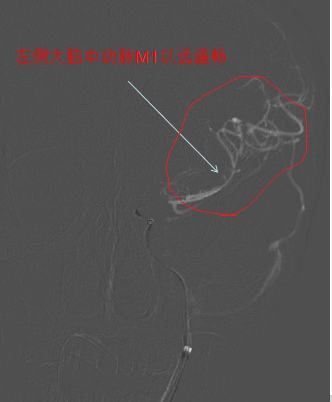

术中影像

刘忠锦副院长带领神经介入小组迅速到达导管室,20分钟后诊断造影确认患者为左侧颈内动脉末端闭塞,47分钟后患者血管内栓子取出,血管再通,前向血流mTICI3级。在神经内科、急诊医学科,导管室和麻醉科通力合作下,手术顺利完成,病人术后复查头CT后送往重症监护室,病情平稳后转回神经内科五病区病房。术后一周,患者脑部功能完全恢复。